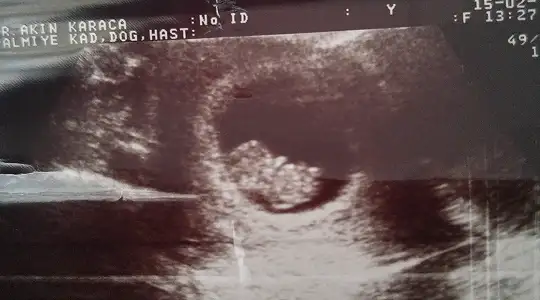

Bebegimi gördum. Minicik daha 9 haftalık olmuş. Kıpır kıpırdı :)) sorun yok dedi doktor. Hamur işi, tatli yeme kilo alma fazla dedi. Bol hareket dedi.

Ayrıca camaşır suyu kullanma dikkat et dedi. Bir ay sonra görüşürüz dedi :)

Can'ım her ultrosonda değişiyor benimde oyle merak etme :) Bi gününden önce çıkıyor Bi gününden sonra :) sıkıntı yok bak Bebisin iyi kalp atışını da duydun icin rahat olsun